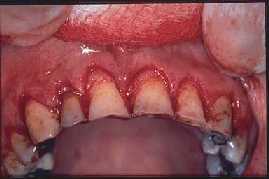

GINGIVECTOMIA

SE RETIRA ENCIA SOBRANTE